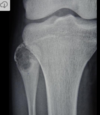

Fratura do platô tibial lateral - Schatzker tipo 2 (traço de fratura + depressão do plato lateral).